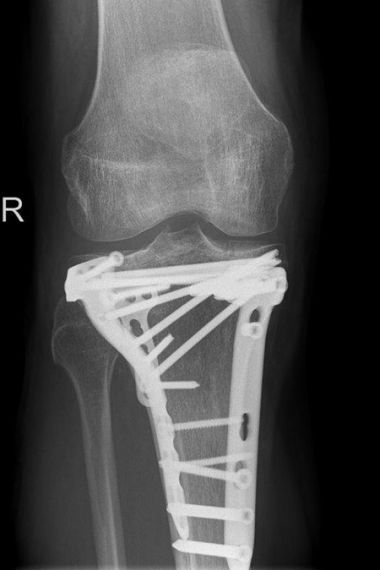

Im April 2022 versorgter außenseitiger Schienenbeinkopfbruch (Tibiakopffraktur) bei einer 35-jährigen Patientin. Bei der Versorgung wurde anhand der CT – Untersuchung die außenseitige kniekehlenwärts gelegene Gelenkflächenabsenkung wieder angehoben und mit Knochen unterfüttert. Intraoperativ wurde mit Hilfe der Arthroskopie die Gelenkfläche überprüft. Anschließend wurde die Rekonstruktion durch die seitliche und hintere Platte sowie zusätzliche Schrauben stabilisiert. Nach der Operation konnte das Knie steigernd bewegt und zunächst mit einer Teilbelastung an Unterarmgehstützen belastet werden. Nach 3 Monaten ist die freie Belastung bei guter Beweglichkeit wieder erzielt worden.